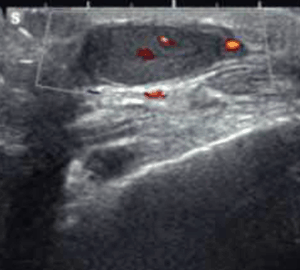

45 años. Masculino. MC: dolor inguinal derecho con irradiación a testículo de dos días de evolución.